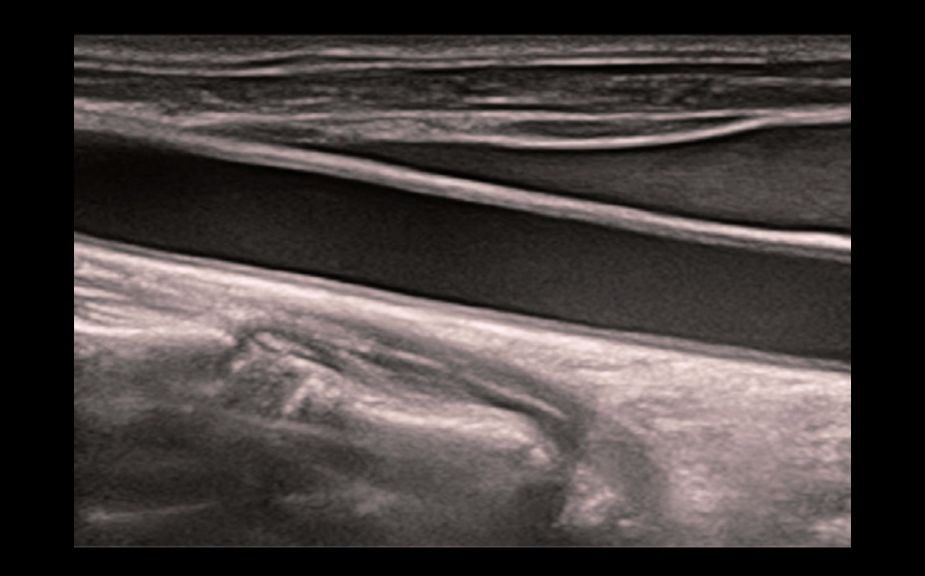

Focal Lesion Diagnosis with Perfusion: UWN+ Contrast Imaging

Utilization of both the 2nd harmonic and non-linear fundamental signals

Greater sensitivity for minor signals and longer agent duration with lower MI

CEUS of metastatic liver cancer

CEUS perfusion of thyroid adenoma